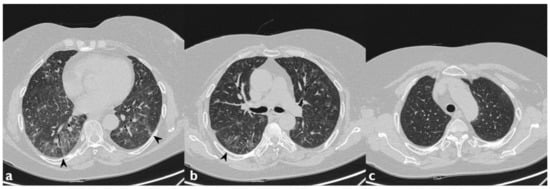

| HRCT Pattern | Associated Drugs |

|---|---|

| Fibrotic pattern | Nitrofurantoin (chronic toxicity), methotrexate, sulfalazina, rituximab, tocilizumab, bleomycin, busulfan, cyclophosphamide (chronic toxicity), amiodarone (form with fibrous course), tocainide, cocaine |

| Organizing pneumonia | Nitrofurantoin (chronic toxicity), methotrexate |

| Mosaic pattern | Nitrofurantoin (acute toxicity), methotrexate, sulfalazina |

| Isolated ground glass | Rituximab, tocilizumab, cyclophosphamide (acute reaction), amiodarone (initial stage), cocaine |

| Alveolar hemorrhage | Penicillamine, rituximab, cocaine |

| Pulmonary edema | Acetyl-salicylic acid, mitomycin |

| Pleural effusion | Sulfonamides, methotrexate |